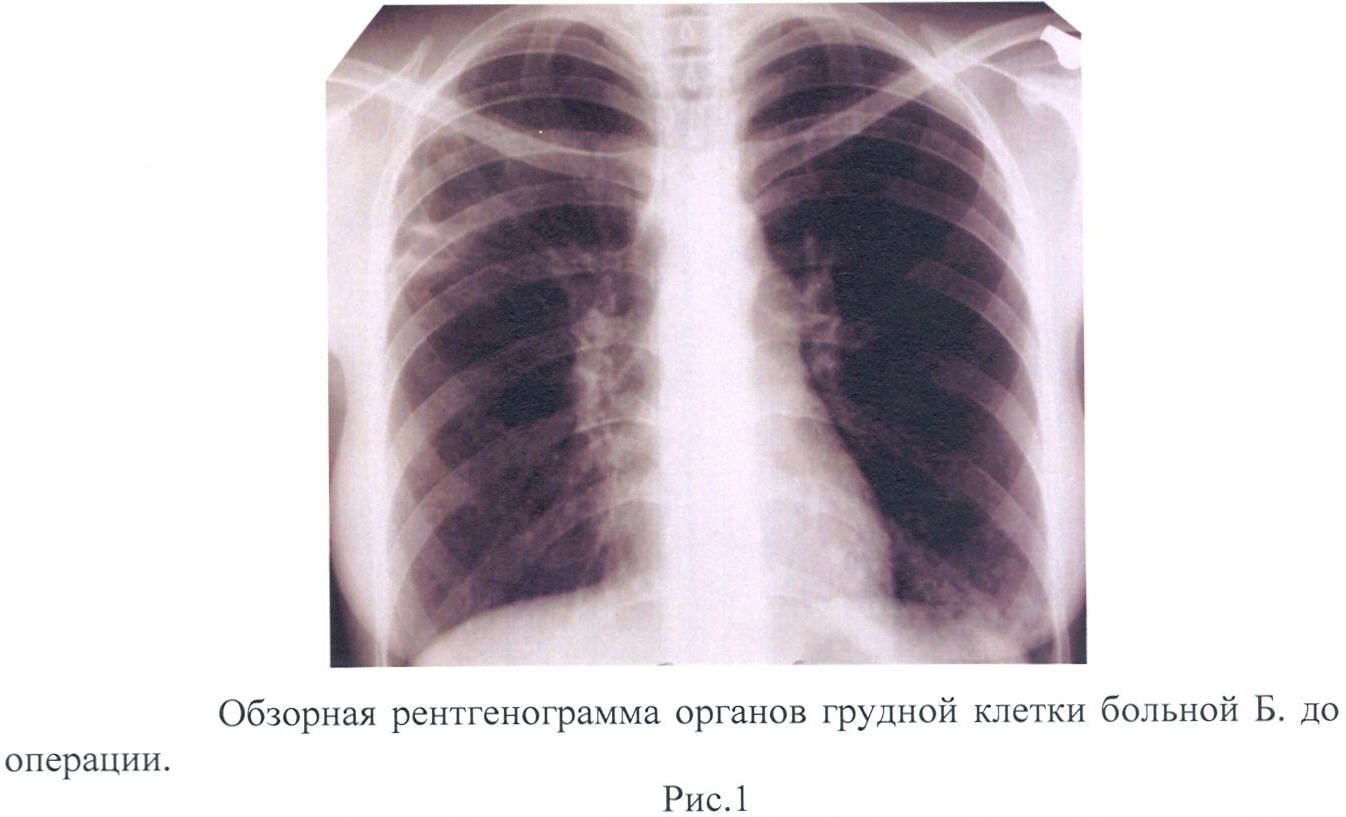

Иллюстрации по теме очагового и инфильтративного туберкулеза